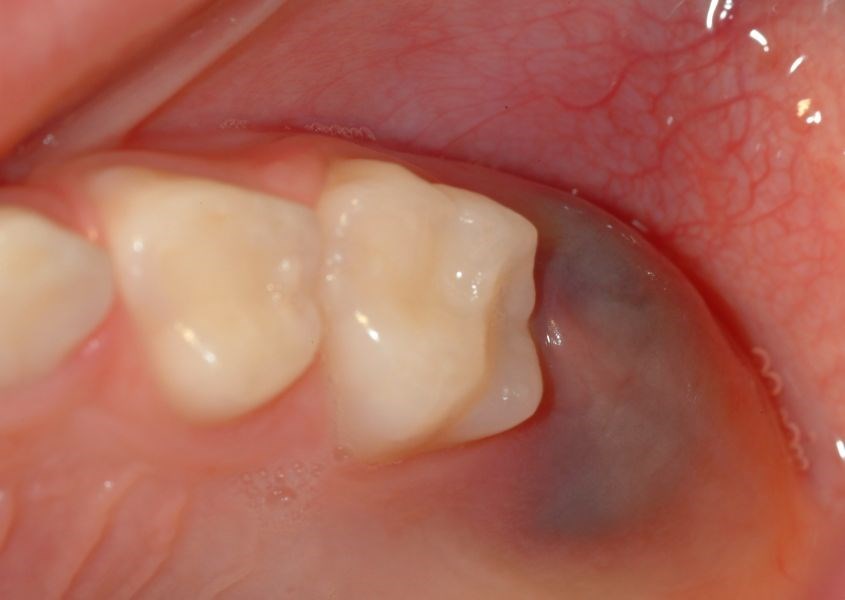

Tại vị trí răng mọc nhú lên của trẻ, nướu bị phồng hoặc lồi ra. Nguồn từ oralanswers

Sưng nướu do mọc răng ở trẻ là tình trạng sưng tấy, xảy ra tại vị trí nướu răng, nơi một chiếc răng sắp nhú lên. Những đặc điểm sau đây cho thấy tình trạng sưng nướu là bình thường do mọc răng ở trẻ: